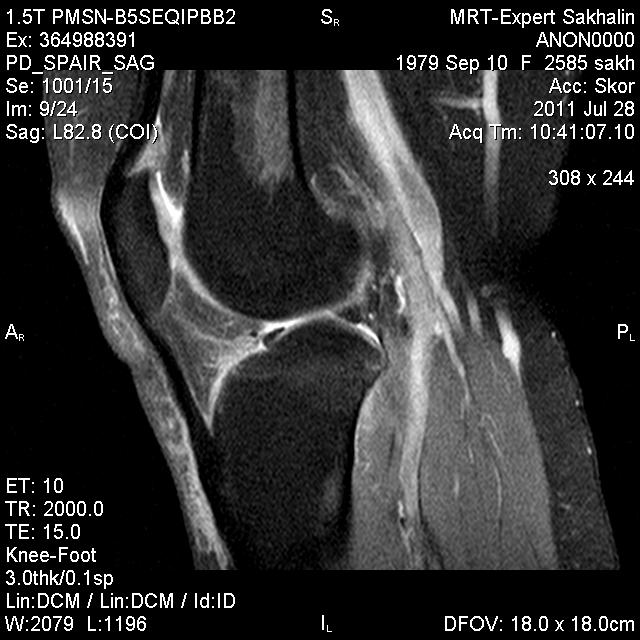

Коленный сустав

Подглядела случай у коллеги.

Что это может быть?

Не вижу криминала. А на что жалуется девушка?

P.S. В костях - это, скорее всего, резидуальный красный костный мозг.

участки гемопоэтического костного мозга